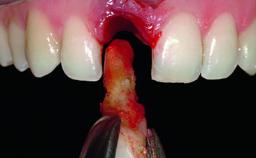

Bone Augmentation Horizontal|Simultaneous|Staged

Augmentation Materials Xenogenous|Membrane

Soft Tissue Grafting Simultaneous

Bone Volume Deficient horizontally, requiring prior grafting